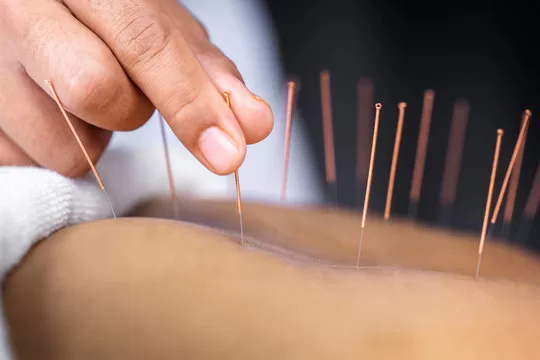

Acupuncture has been around for thousands of years, but in recent decades it has stepped into the spotlight of modern medicine. Once dismissed as “alternative” acupuncture is now being studied in hospitals and universities all over the world. The results? Evidence-based studies now prove that acupuncture delivers real benefits, from pain management and faster recovery to better mental health.

So, what does the science say? Let’s take a look at some of the most exciting studies that validate acupuncture therapy.

Pain is the area where acupuncture has the strongest evidence. A recent systematic review and meta-analysis found that acupuncture significantly reduced pain compared to sham treatments, and patients reported fewer side effects than those taking conventional painkillers.

Another large-scale review covering 111 studies showed that acupuncture offers consistent short-term relief for conditions like:

One trial on patients with chronic sciatica found that after just 10 sessions in four weeks, participants reported less pain and improved mobility.

Knee Osteoarthritis

Knee osteoarthritis is one of the most common conditions treated with acupuncture. A 2025 meta-analysis looked at 18 clinical trials and found that combining acupuncture with moxibustion (a heat-based therapy) significantly reduced pain and improved mobility. These improvements continued for more than a year, offering longer-lasting relief compared to many common treatments.

Migraine

If you suffer from migraines, you’ll be glad to know that studies suggest acupuncture can prevent attacks. Compared to sham acupuncture, real treatments slightly reduced the frequency and intensity of migraines. Some reviews even found acupuncture to be as effective as medication but without the side effects.

The science is catching up with what practitioners and patients have known for centuries: acupuncture works. From chronic pain and arthritis to migraines, anxiety and even stroke recovery, the latest studies show that acupuncture goes beyond tradition and stands as an evidence-based, effective treatment.

For anyone considering acupuncture, the best advice is to consult a certified practitioner and look at it as a complementary therapy alongside conventional care. With increasing evidence from modern studies, acupuncture has shifted from being viewed as “alternative medicine” to becoming a trusted pillar of integrative healthcare.